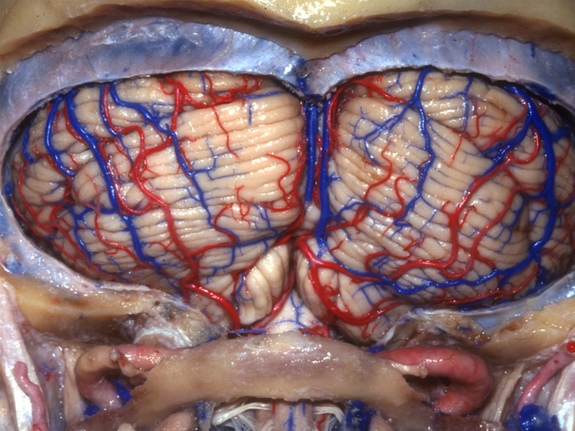

El cerebelo, es una región del cerebro importante para el control motor, se ve como un órgano separado, pegado en el cerebro por debajo de los dos hemisferios. Esta imagen muestra la “superficie suboccipital” del cerebelo, es decir, visto desde abajo. El cerebelo no inicia el movimiento, pero esta región del cerebro gobierna la coordinación y la sincronización apropiada.

Aquí podemos ver nuevamente al cerebelo, visto desde su base el sitio donde se une al cerebro. Una gruesa capa de tejido conocido como duramadre, separa al cerebelo del cerebro. El cerebelo obtiene información de otras partes del cerebro, a través de conexiones con una parte del tronco cerebral llamada protuberancia.